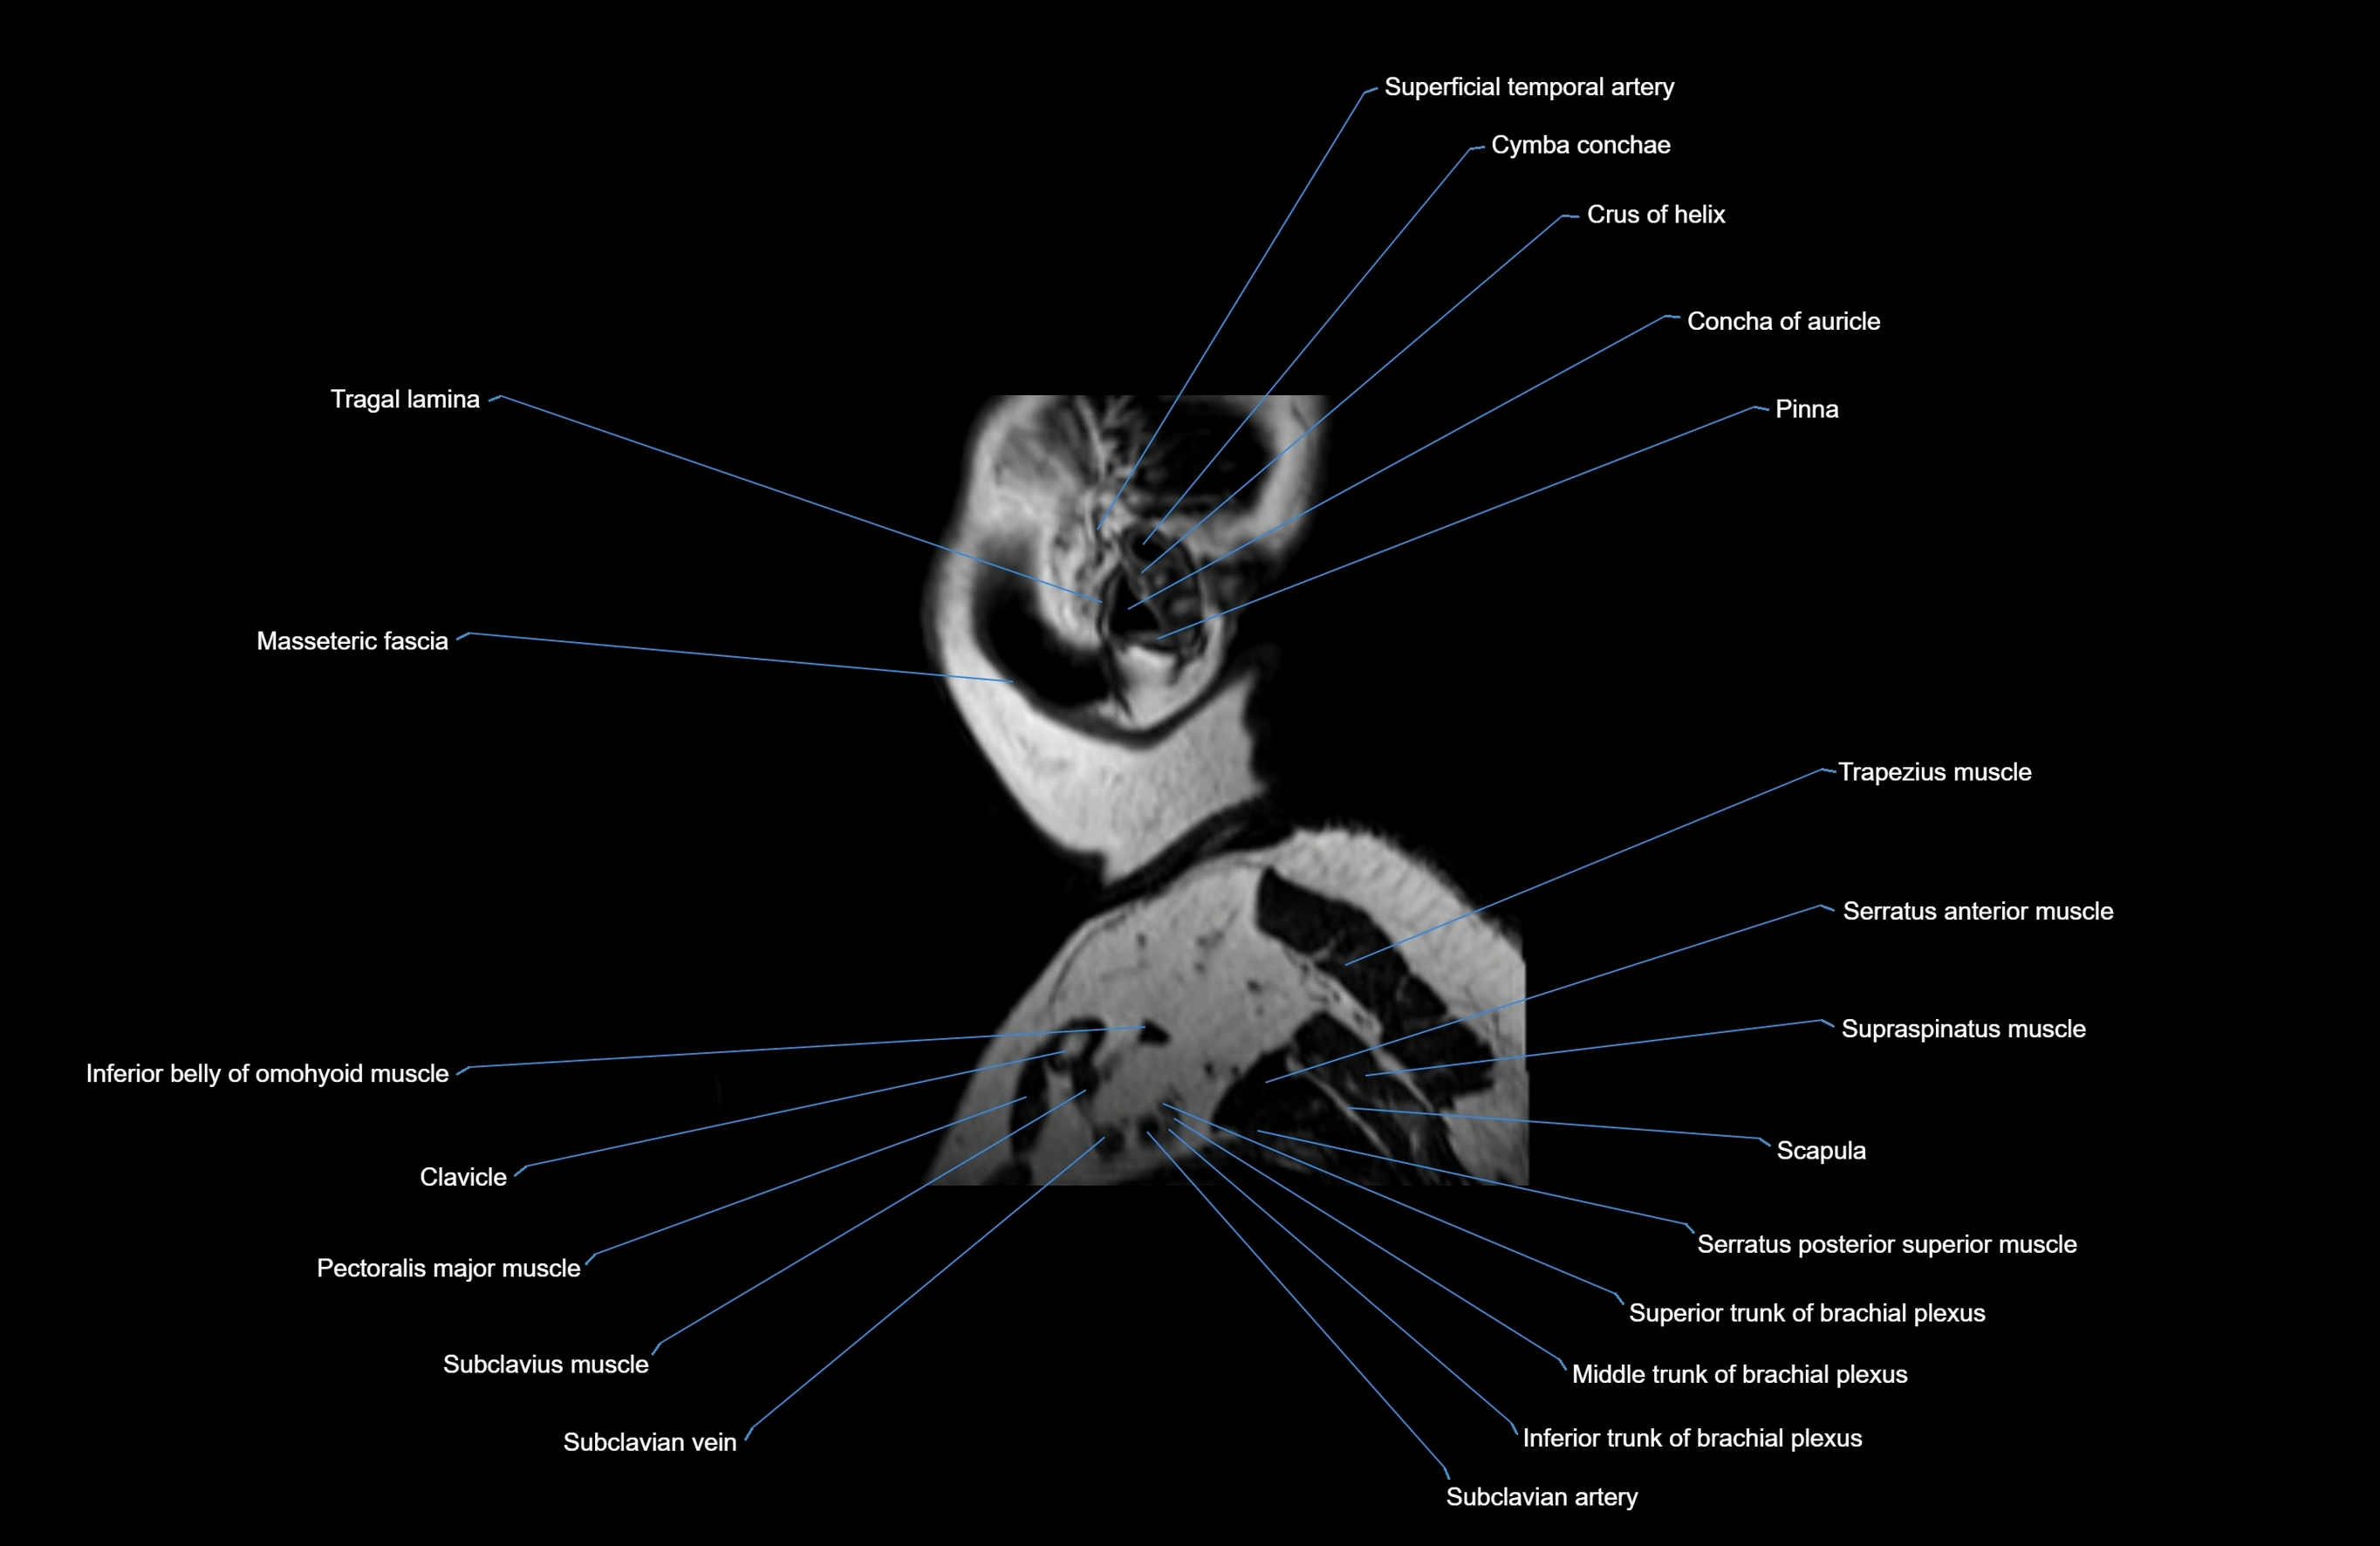

- Axillary artery

- Axillary veins

- Brachial plexus

- Clavicle

- Pectoralis major muscle

- Scapula

- Serratus anterior muscle

- Serratus posterior superior muscle

- Subclavian artery

- Subclavius muscle

- Superficial temporal artery

- Supraspinatus muscle

- Trapezius muscle